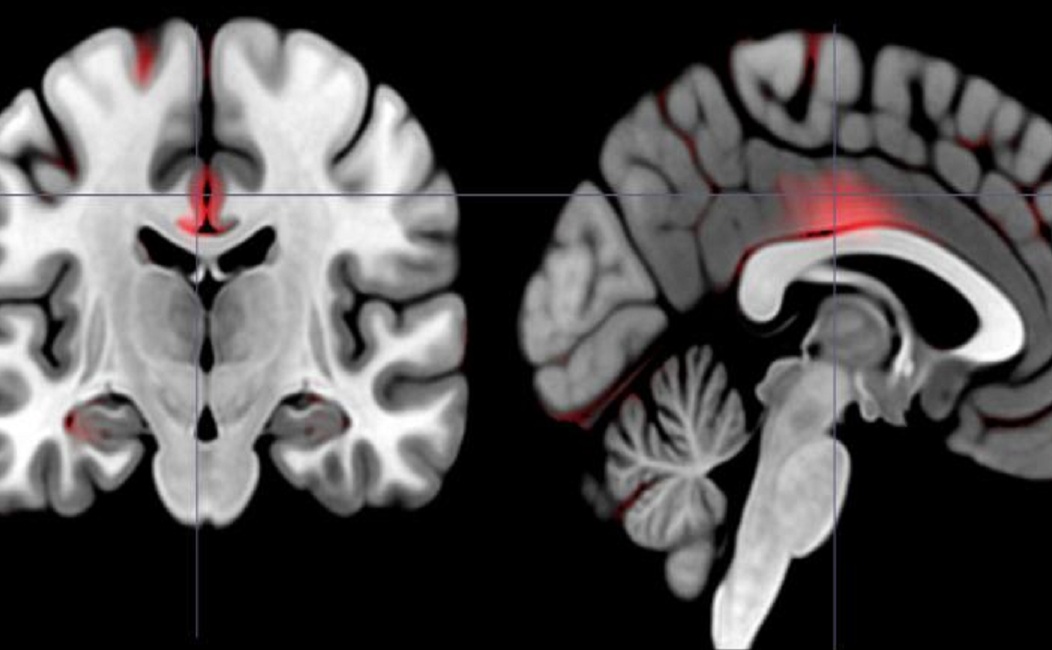

Las áreas marcadas en rojo reflejan mayores cantidades de materia gris en personas extrovertidas "dinámicas". Imagen: Laboratorio White. Fuente: Universidad de Brown.

Los sujetos se sometieron a resonancias magnéticas diseñadas para detectar el volumen de materia gris en diferentes regiones de su cerebro. Gracias a la literatura psicológica sobre la extroversión, White y Erica Grodin, estudiante de posgrado, sabían que querían mirar en regiones de interés, como la corteza orbitofrontal medial, que participa en la toma de decisiones basadas en la recompensa, pero también hicieron un análisis general de todo el cerebro usando una técnica llamada morfometría basada en voxel (VBM, por sus siglas en inglés).

Como era de esperar, encontraron que un mayor grado de uno u otro tipo de extroversión se correlacionaba significativamente con un mayor volumen de materia gris en el lado derecho y el izquierdo de la corteza orbitofrontal medial, incluso después de controlar por posibles factores de confusión como la edad.

Pero entre las personas con mayores puntuaciones en extroversión dinámica, también encontraron varias otras regiones que tenían volúmenes de materia gris significativamente mayores: el giro parahipocampal (que participa en el aprendizaje y la memoria de recompensa); la circunvolución precentral, el giro cingulado y el caudado (que participan en el control cognitivo de la conducta y la iniciación, planificación y ejecución de movimientos voluntarios hacia objetivos); y, entre los hombres del estudio, el núcleo accumbens (implicado en la recompensa por incentivos).

Así, mientras que los dos tipos de personas extrovertidas tenían mayores volúmenes en una región clave del cerebro, los extrovertidos dinámicos tenían también mayores volúmenes en varias otras áreas. White y Grodin encontraron muchas de esas otras áreas a través del análisis VBM de todo el cerebro.